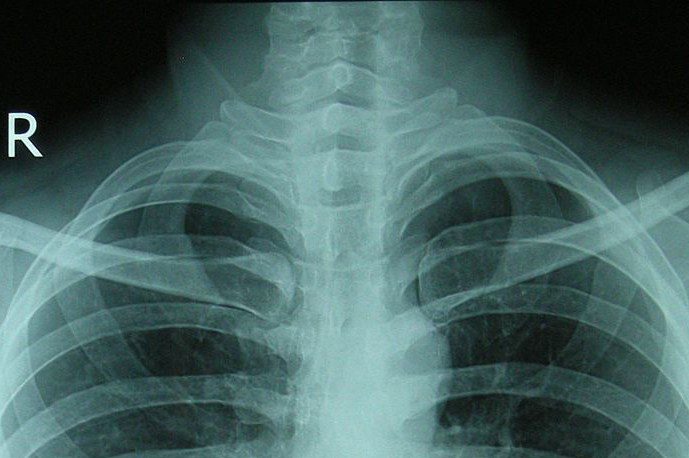

Postoperative pulmonale Komplikationen (PPC) sind eben die häufigsten mittelfristigen Komplikationen nach großen Operationen und schwere PPCs treten bei 2,8% aller Patienten auf. Wenig überraschend verschlechtern sie sowohl Morbidität als auch Mortalität, sie tun dies interessanterweise jedoch noch stärker als kardiale Komplikationen.

Neben einem möglichst niedrigen FiO2 macht aber auch die Anwendung anderer aus der ARDS Therapie bekannten, lungenprotektiven Strategien intraoperativ Sinn. Die Kombination aus niedrigem Tidalvolumen, Recruitmentmanövern und PEEP konnte zumindest in einer Patientengruppe mit erhöhtem Risiko für postoperative pulmonale Komplikationen das Risiko um 69% senken. Ähnlich wie aktuelle Arbeiten beim ARDS zeigen, scheint jedoch auch intraoperativ der Beatmungsdruck (Peak pressure, aber wahrscheinlich vor allem driving pressure) der bessere Parameter zur Steuerung zu sein als das Tidalvolumen. Der beste intraoperative PEEP konnte bis jetzt noch nicht gefunden werden, was wahrscheinlich daran liegt dass es diesen einen Wert eben nicht gibt, sondern der ideale PEEP für jeden Patienten individuell gefunden werden muss, aber hier erwarten wir noch einige Studien in der nächsten Zeit.

Bei Patienten mit pulmonalen Risikofaktoren, welche bereits ein hohes Risiko respiratorischer Komplikationen mitbringen, ist sicherlich die wichtigste, weil fundamentalste Strategie perioperativ wenn möglich eine Beatmungsnotwendigkeit überhaupt zu verhindern und großzügig regionalanästhesiologische Techniken einzusetzen. Aber auch die Kombination aus Vollnarkose mit regionalanästhesiologischen Verfahren kann hier vorteilhaft eingesetzt werden.